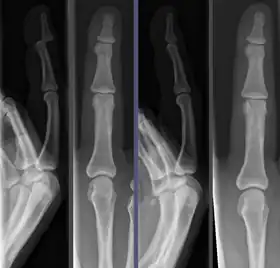

Joint dislocation in the DIP of the third finger before (left images) and after (right images) reduction.

Once the fragments are reduced, the reduction is maintained by application of casts, traction, or held by plates, screws, or other implants, which may in turn be external or internal. It is very important to verify the accuracy of reduction by clinical tests and X-ray, especially in the case of joint dislocations.